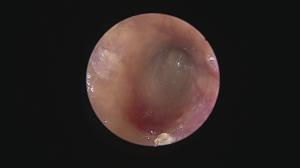

一言で外耳炎と言っても・・原因は様々・・ですよね。

繰り返す外耳炎で意外と知られていない原因に「ゴミの蓄積」があります。

ゴミと言っても成分は細菌、脂、汗、毛、炎症細胞・・などなどが混じって形成されています。

そのゴミが鼓膜付近に蓄積していると、点耳薬や洗浄(一般的は)は効果を十分に発揮できません。

まずはこの汚れをしっかり除去することが重要ですね。

この除去はやはり大変です・・鼓膜があるのと、耳の道が狭いこと(晴れている場合も多い)、動くのでそもそも無理・・

道内では珍しい耳道内視鏡治療を積極的に行っています(麻酔下で初めに除去することでその後のケアが楽になるので他施設で行っていない施術を当院では取り入れています)

これがなかなか技術が必要ですが、処置後の経過が良いことがモチベーションになります!

この耳道内視鏡はあまり知られていませんが、お困りの症状にあった処置ができますので今後もアナウンスしていきます!

道内遠方の方も来院されますので、遠くの方でお困りの症状がございましたらまずはご連絡くださいませ。